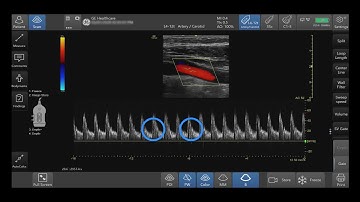

Venue Family Tutorials: Optimizing Color PDI